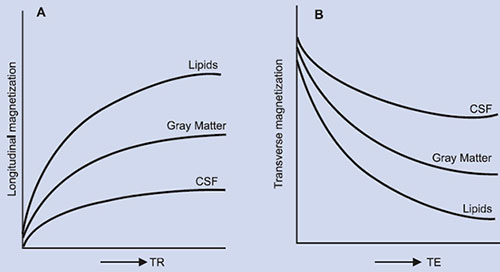

The primary sources of inherent tissue contrast in MRI are three-fold: proton (spin) density (PD), T1 and T2. Unlike PD which may vary by just a few percent between various tissues, T1 and T2 relaxation times can vary as much as more than 100% among soft tissues (Table 1.2), and can have important effect on image contrast (Fig. 1.3). For example, the T1 of CSF is several times greater than white matter. Similarly, edema has higher T1 and T2 than normal white matter. Few types of lesions, such as lipomas, melanomas, and fibrous lesions deviate from this general rule of having higher T1 and T2 values than the surrounding normal tissues. Although data on proton density are limited, it often occurs that PD values are also directly correlated with relaxation times. For example, normal tissues or lesions having longer T1 and T2 values also tend to have higher PD values as has been demonstrated for brain white matter lesions20 and appear to be generally true for most other lesions.

Fig. 1.3: Relative MR signal intensities of tissues: (A) as a function of the repetition time (TR) and (B) as a function of the echo time (TE).

The pixel intensity in a MR image is a function of T1, T2 and image acquisition parameters (vide infra) such as TR (time of repetition) and TE (time of echo). In routine MRI, the images obtained are either PD, T1-weighted or T2-weighted. They usually do not refer to images that display PD, T1 or T2. Instead, the terms refer to the relative weight with which the three parameters affect the tissue contrast in MR images. Such images are obtained by varying the parameters TE and TR. Generally, tissues with short T1 will appear bright on T1- weighted image, and tissues with long T1 will appear dark. For example, in a T1- weighted image of the brain, the fat will appear as white; white matter as light gray and gray matter as gray and the CSF as black as shown in Figure 1.4A. In T2-weighted image of coronal section of the brain (Fig. 1.4B), fat appears as gray while the white matter as dark gray; the gray matter appears as gray and the CSF as white. T1-weighted images are useful for viewing the anatomy (morphology) while T2 images are useful for identifying the tissue pathology.